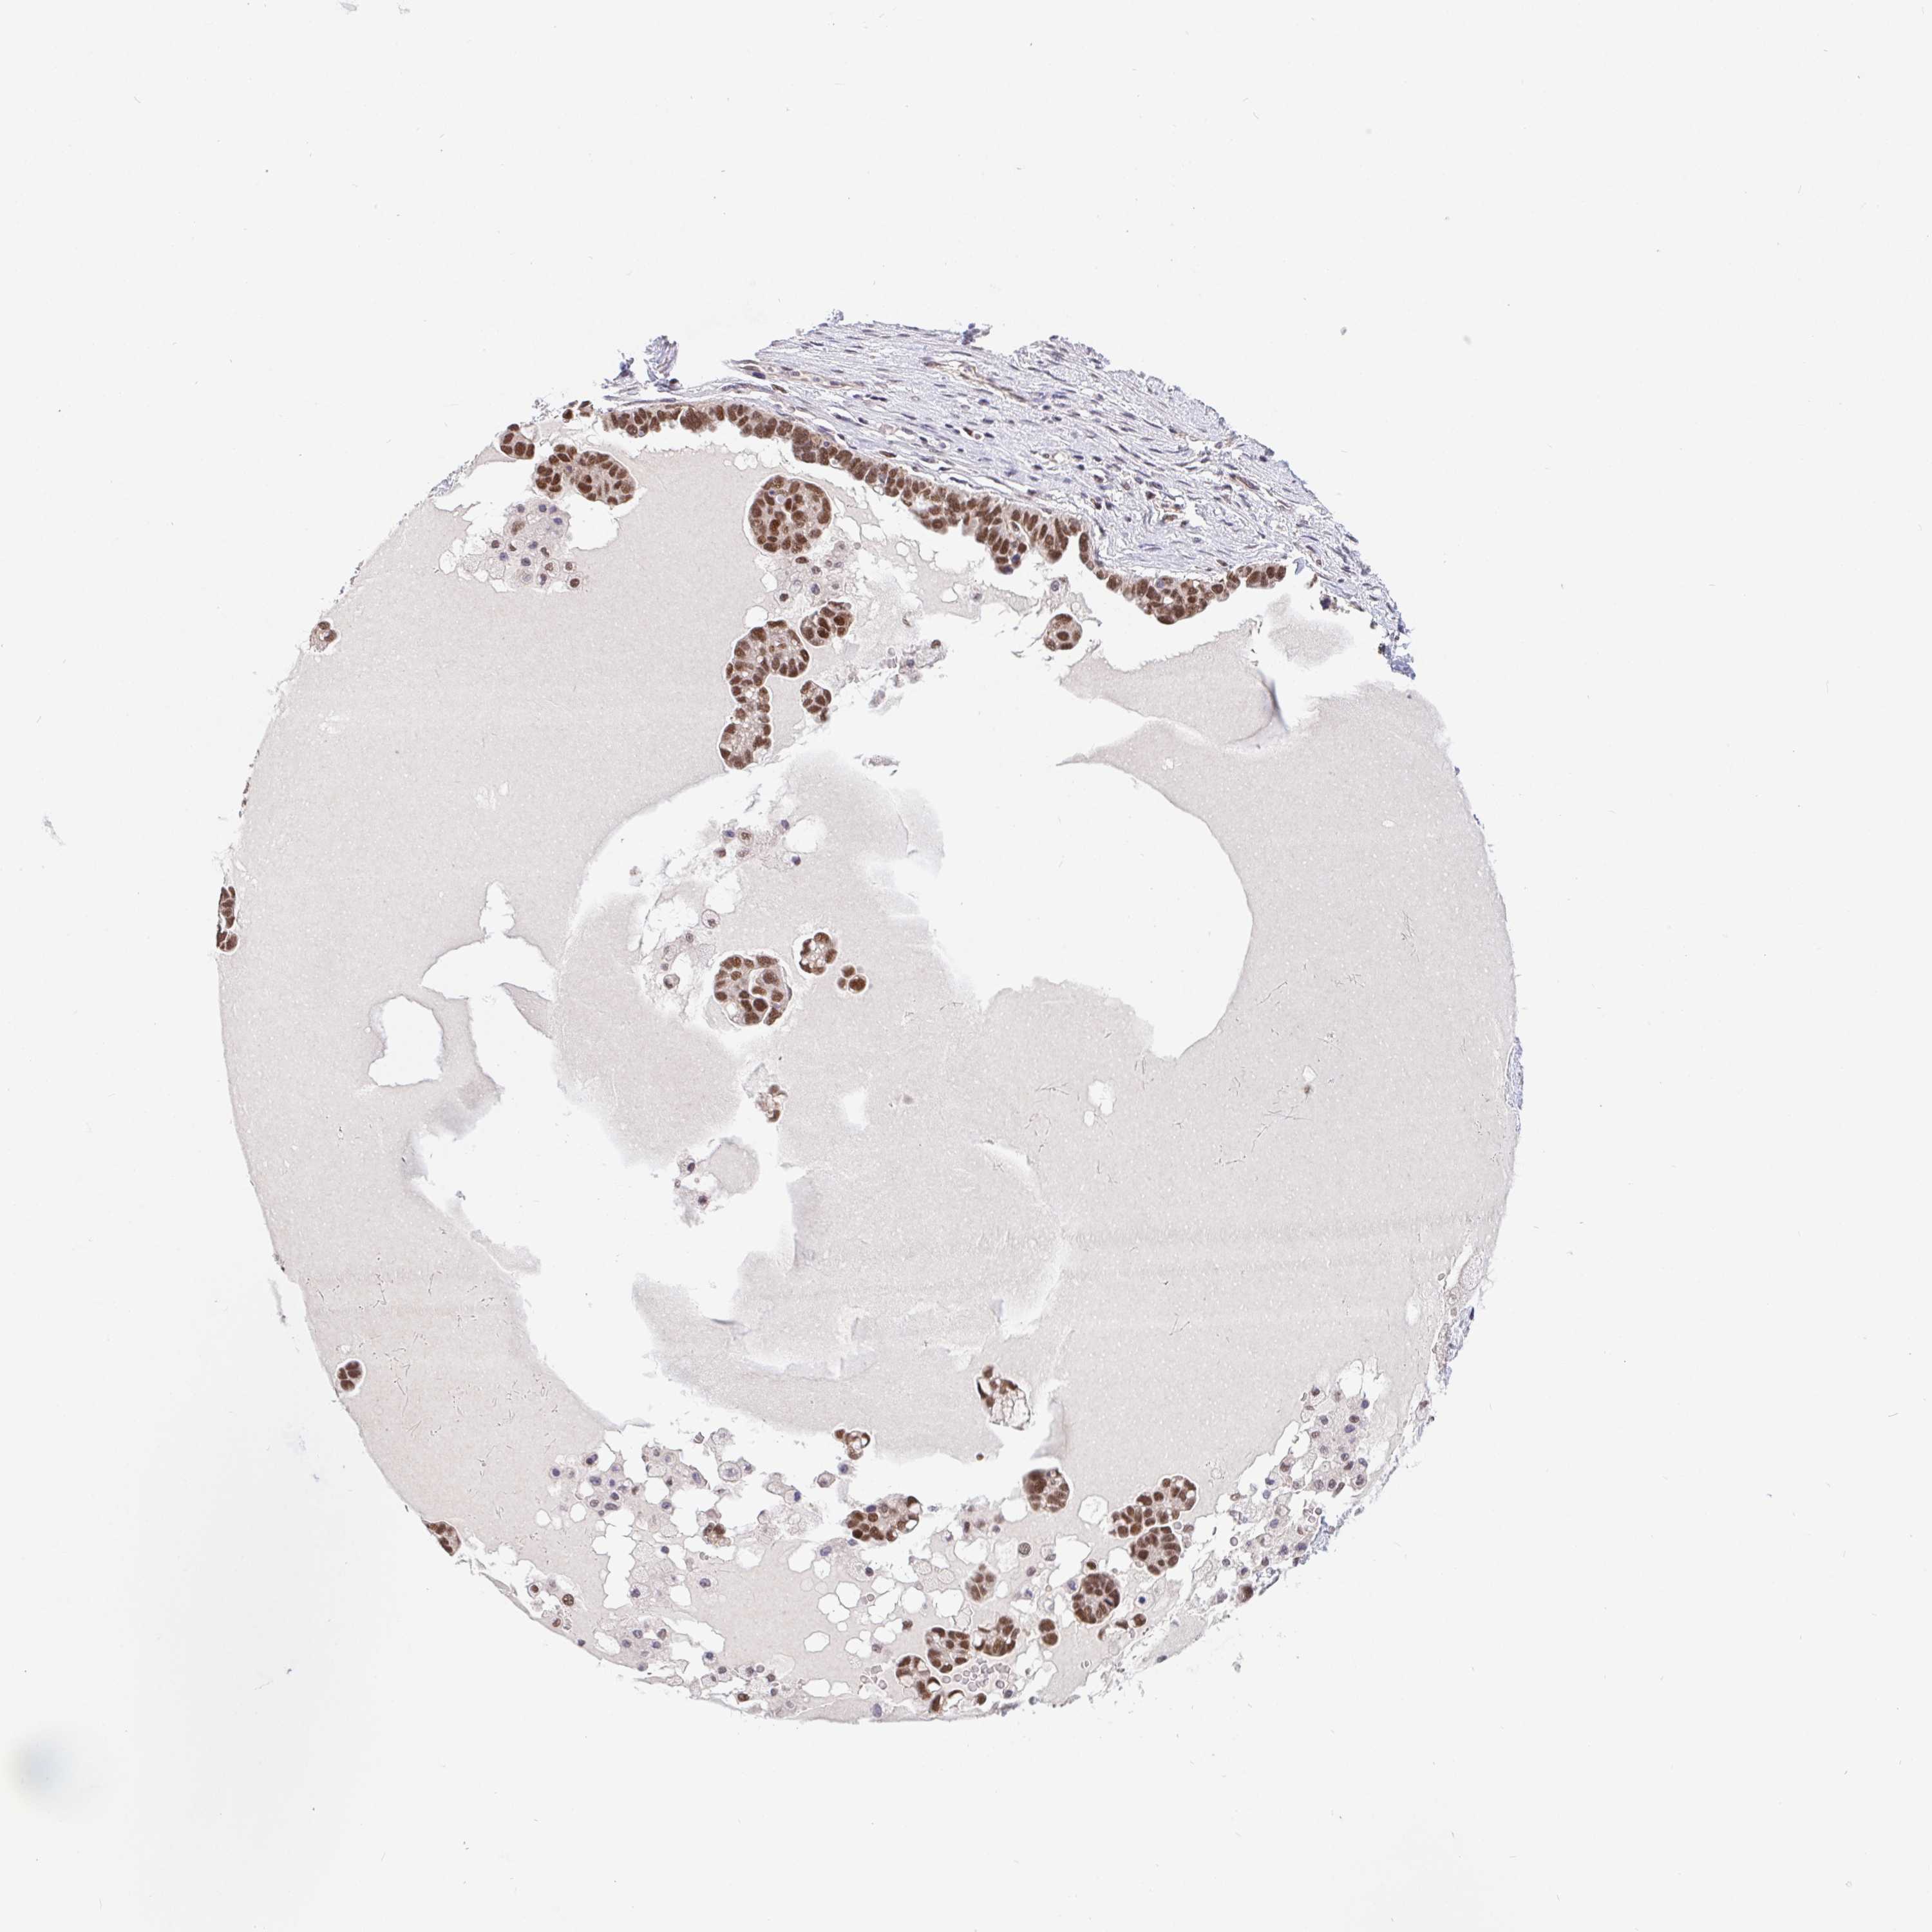

OVARIAN CANCER - Protein expressioni

A mouse-over function shows sample information and annotation data. Click on an image to view it in a full screen mode. Samples can be filtered based on level of antibody staining by selecting one or several of the following categories: high, medium, low and not detected. The assay and annotation is described here.

Note that samples used for immunohistochemistry by the Human Protein Atlas do not correspond to samples in the TCGA dataset.

Antibody stainingi

Antibody staining in the annotated cell types in the current human tissue is reported as not detected, low, medium, or high, based on conventional immunohistochemistry profiling in selected tissues. This score is based on the combination of the staining intensity and fraction of stained cells.

Each image is clickable and will lead to virtual microscopy that enables deeper exploration of all samples and also displays staining intensity scores, fraction scores and subcellular localization as well as patient and tissue information for each sample.

Antibody HPA064323

Antibody CAB002608

Staining

High

Location

Cystadenocarcinoma, serous, NOS

Cystadenocarcinoma, mucinous, NOS

Carcinoma, endometroid